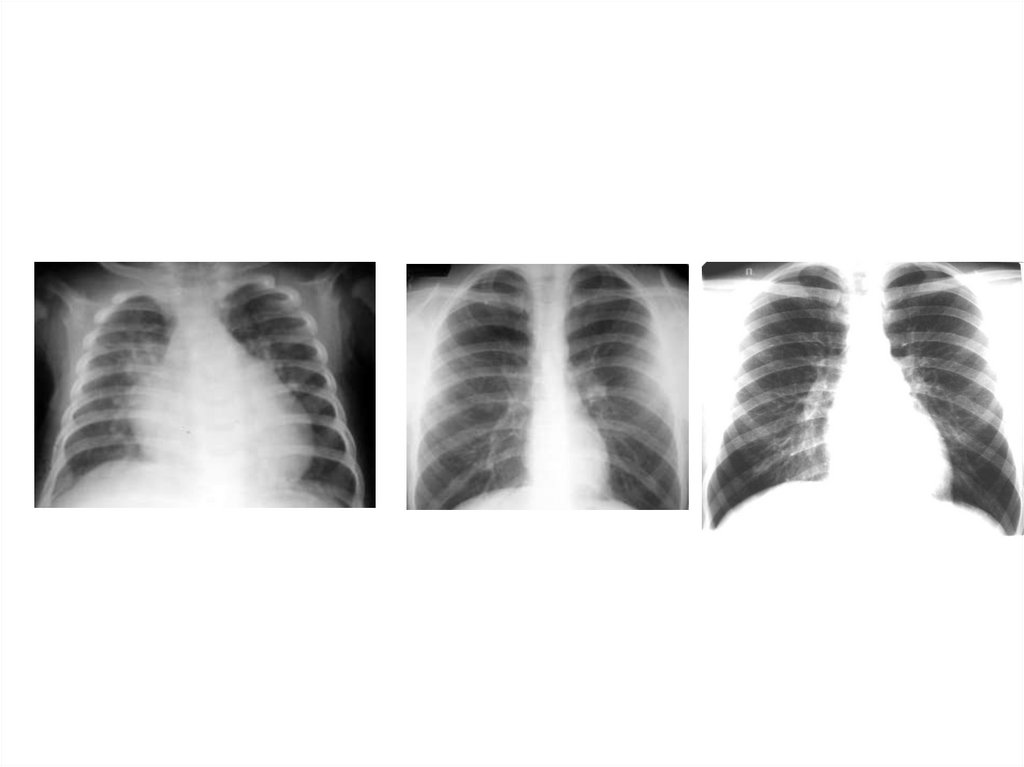

Рентгенография

Рентгеноскопия